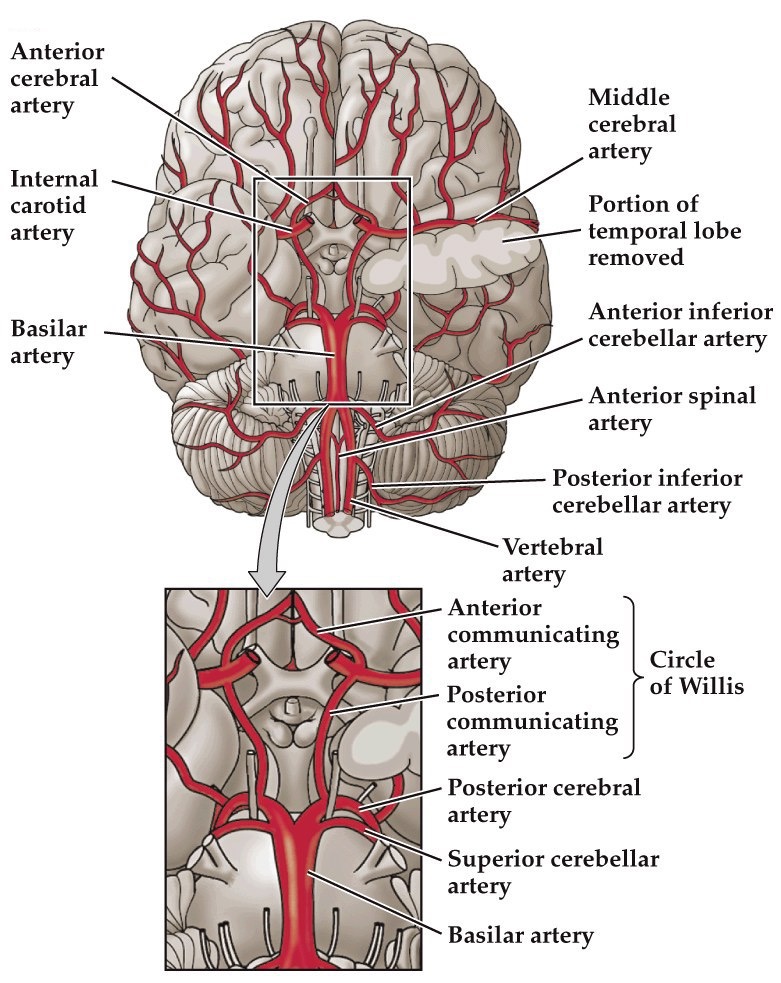

Cerebral circulation